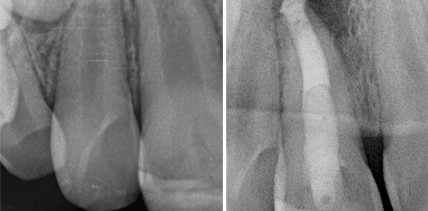

Apexifikation mit MTA nach Trauma am jugendlichen Zahn

Frontzahntraumata im Kindes- und Jugendalter sind keine Seltenheit: Bis zu ein Drittel dieser Altersgruppe erleidet früher oder später traumatische Verletzungen. Warum eine Apexifikation mit MTA eine gute Alternative zu herkömmlichem Kalziumhydroxid ist und was bei diesem Verfahren zu beachten ist.

Jahr 2016, Ausgabe 03, Seite 6 Autoren: Dr. Julia Basel, M.Sc.